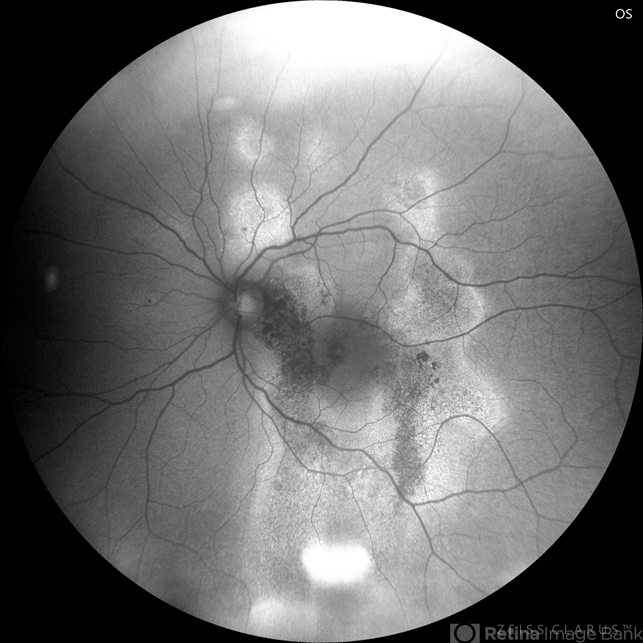

- chronic central serous chorioretinopathy (CSCR)

- Fundus autofluorescence of a 43-year-old man with chronic central serous chrorioretinopathy, with recurrent episodes since 2020.